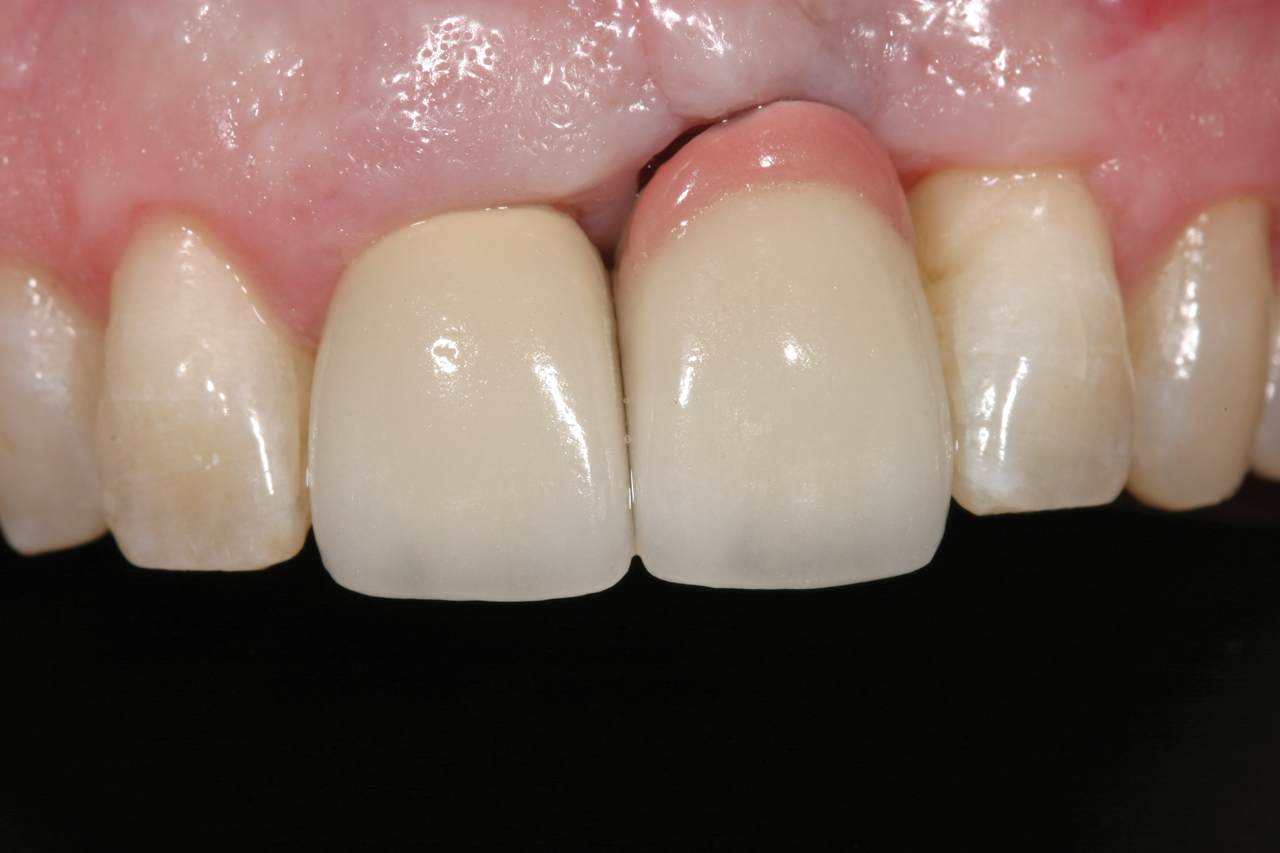

Fig 6. Gingival-colored porcelain was used to restore an implant site where fractured maxillary anterior teeth Nos. 7 and 8 remained too long. Although the result was functionally successful, it was considered an esthetic compromise.

Figure 6

Fig 7. The gingival-colored porcelain was slightly visible upon smiling. This patient’s high smile line should have been the determining factor in the decision to restore or extract.

Figure 7